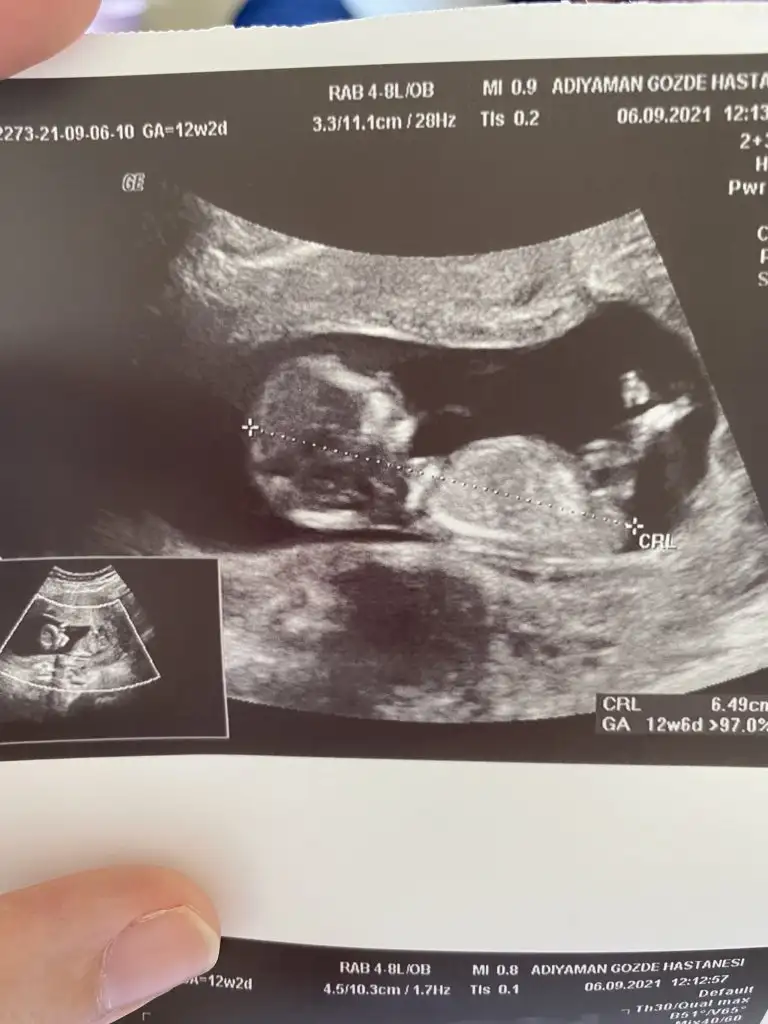

Kızlar benimkinede bakar mısnz? Karın ultrasonu 12+2 de yiz.

Eklentiler

• 67C7BD9F-AC6D-4A5A-9B03-A91019DC907A.webp

67C7BD9F-AC6D-4A5A-9B03-A91019DC907A.webp

36,9 KB · Görüntüleme: 100

Bi fikri olan varmı kızlar ben anlamadım nubtan